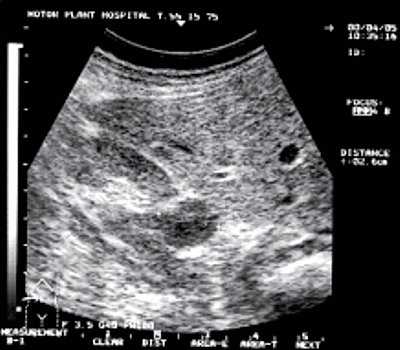

- Инструментальные исследования. К диагностике первой линии относят ТРУЗИ. Ультразвуковое сканирование показывает типичные признаки воспаления: увеличение и отек везикул, негомогенность их содержимого, усиленную васкуляризацию. Методика дает возможность одновременно оценить состояние предстательной железы. Диагноз подтверждает везикулоскопия, позволяющая визуализировать изменения в везикулах. МРТ и КТ малого таза производят при подозрении на сопутствующий опухолевый процесс или врожденные аномалии развития.

Поэтому в указанных отделах гипоэхогенные канцероматозные очаги могут не визуализироваться. Косвенными признаками опухолевого поражения предстательной железы являются изменения семенных пузырьков, которые отчетливо визуализируются при трансабдоминальном и трансректальном сканировании. Патологические процессы приводят к изменению формы, размеров, структуры семенных пузырьков и симметричности относительно срединной линии. При этом нарушается сократимость семенного пузырька с понижением его эхогенности, иногда в сочетании с кистозными изменениями.

Методом ТРУЗИ отчетливо определяются даже небольшие по размерам опухолевые очаги в периферических зонах. В ряде случаев они имеют признаки инфильтративного роста, с распространением на внутреннюю поверхность капсулы предстательной железы или ее прорастанием. Локальное утолщение капсулы и нечеткость наружного контура, как и патологические изменения семенных пузырьков, являются важными критериями в оценке стадии заболевания.